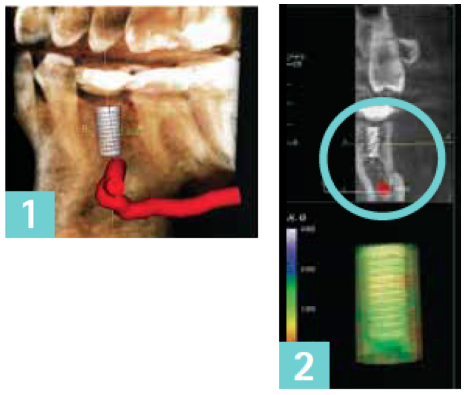

The case presented represents a typical instance where an implant is required in the area of the first or second premolar. A three-dimensional scan is used to accurately locate the exact position of important anatomic structures or landmarks. The 3D scan and software allow moving, slicing, and viewing the anatomy from any direction.

A critical step is the ability to mark the position of the nerve (marked in red in the images below) — this becomes especially helpful when virtual implants are used. A first look might indicate that the implant on this image (1) could interfere with the inferior alveolar nerve and mental foramen. This is not the case. This image (2) is a disto-facial view of the 3D scan showing appropriate clearance between the implant, inferior nerve, and the mental foramen — as indicated by the mint circle. In addition, the Invivo5 software provides a visual indication of such clearance by coloring green the implant model in the lower left of the screen. |